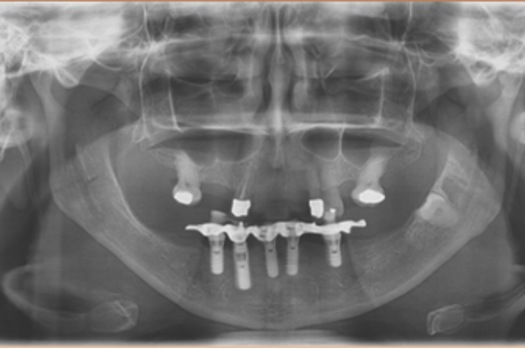

This is an example of a bigger case – one where we wanted to be able to incorporate the fixture position of the implants into the model.

You can see in the series of images below, courtesy of Ashley Bryne, how we did this.

So now we had the benefits we were seeing with routine work and in our implant cases/combined cases.